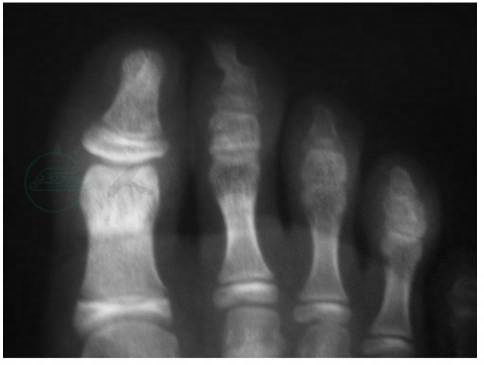

本病容易误诊为甲下寻常疣或化脓性肉芽肿。有时要和血管球瘤或指头黑素瘤鉴别,诊断可疑时可用X线检查,可见一个圆形骨性结节附着于趾骨(图2)。

图2甲下外生骨疣X线片